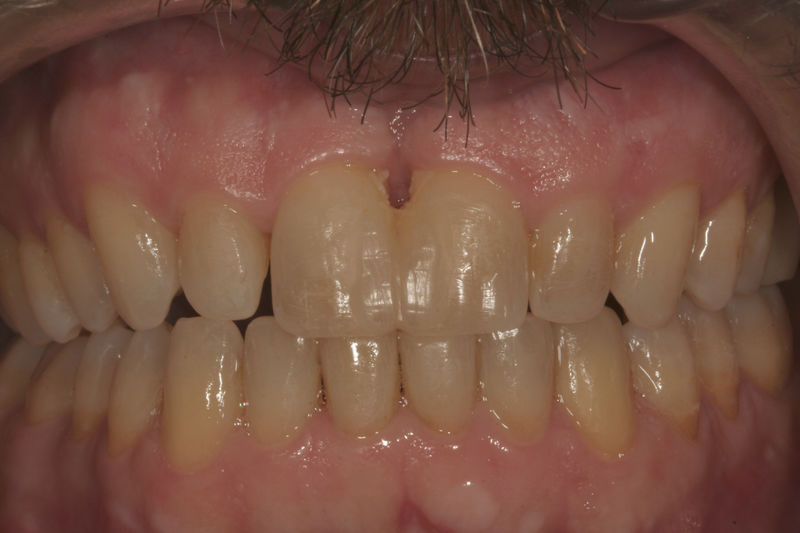

Amplia gama de tratamientos para mejorar la apariencia de la sonrisa, corrigiendo el color, la forma, el tamaño, la alineación y la posición de los dientes. Los procedimientos más comunes y solicitados incluyen el blanqueamiento dental, las carillas y coronas, así como las resinas.

Son restauraciones que cubren toda la cara frontal del diente, generalmente empleadas en el sector anterior y cuya finalidad es primariamente estética.

Restauraciones fabricadas en el laboratorio con materiales estéticos, los cuales cubren de manera total dientes anteriores y posteriores. Se utilizan primariamente para restaurar dientes con caries, fracturas y/o defectos amplios, así como soportes de puentes. Para poder enviar el caso al laboratorio se toman impresiones utilizando materiales de impresión o técnicas modernas digitales.

Implantes, ortodoncia y coronas.

Ortodoncia y coronas.